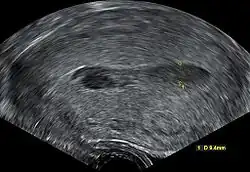

| Transvaginal ultrasonography of a hematometra after childbirth, seen as a hypoechoic (darker) area within the uterine cavity. The cervix is located to the left in the image, and the fundus is located to the right. | |

Although hematometra can often be diagnosed based purely on the patient's history of amenorrhea and cyclic abdominal pain, as well as a palpable pelvic mass on examination, the diagnosis can be confirmed by ultrasound, which will show blood pooled in the uterus and an enlargement of the uterine cavity.[5][6] A pyelogram or laparoscopy may assist in diagnosing any congenital disorder that is suspected to be the underlying cause of the hematometra.[3]